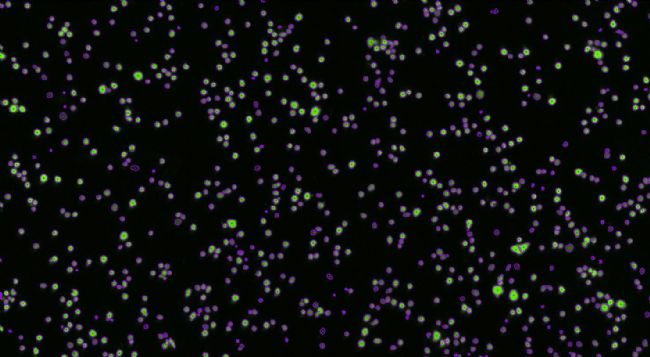

2)0h靶細胞計數圖像(取局部圖像)

綠色熒光細胞圖像 圈定的計數的細胞圖像